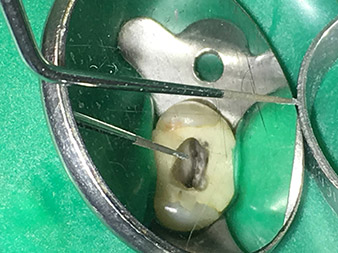

Dr. Nouraie: Die Ultraschall-Endodontie stellt für mich eine optimale Ergänzung zu den bisher verwendeten Techniken dar. Durch den Einsatz des erweiterten Endospitzen-Sortiments von W&H lässt sich die Qualität der Behandlung und somit die Langzeitprognose der Zähne deutlich verbessern. Die Spitzen zeichnen sich durch eine sehr hochwertige Verarbeitung aus und sind absolut empfehlenswert.

Besonders positiv sehe ich die Abtragleistung, die selbst nach häufigem Einsatz konstant bleibt, zudem gestaltet sich die Wiederaufbereitung der Instrumente sehr einfach und wirtschaftlich.

Fotos: Dr. Shahrad Nouraie Ashtiani, Bremen